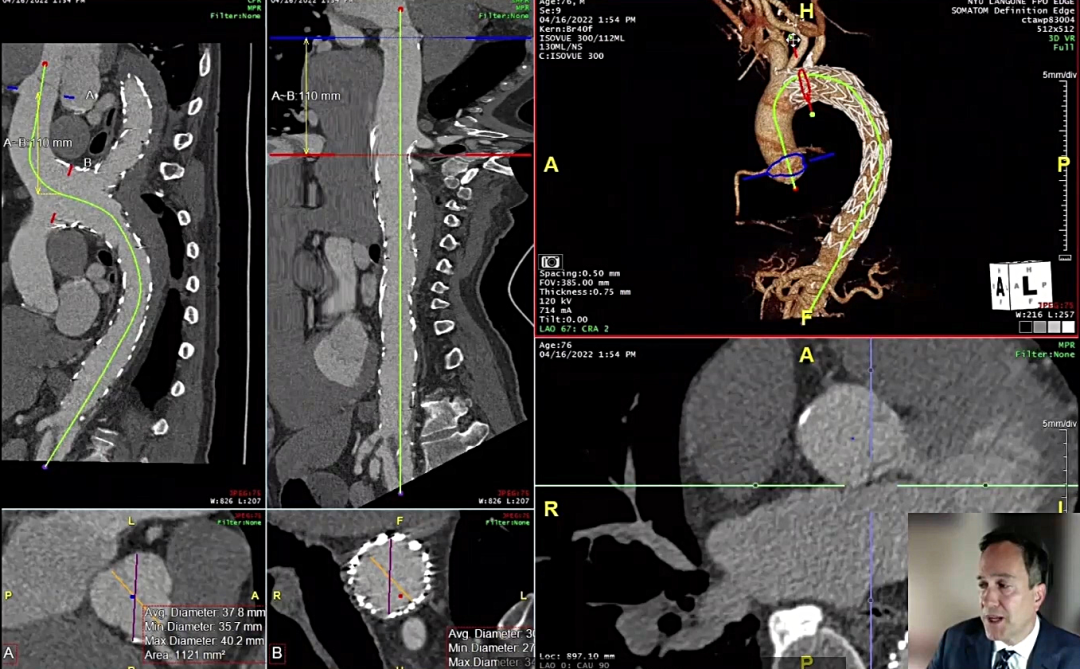

病情分析:通过CTA图,可以看到患者的真腔非常狭小

(术前CTA图)

治疗方案:最初想采用袖套+缝合的方式,但是由于没有办法获得市售的COOK产品,故而最终采用了吴医生及同事的技术